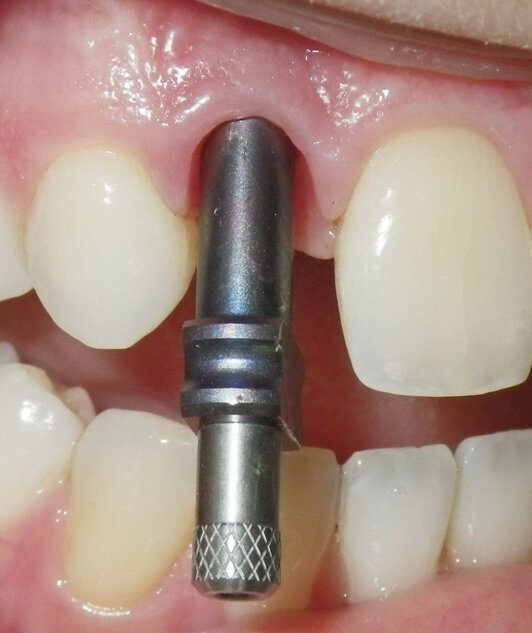

A pickup impression coping was secured to the implant and seating was verified (Fig. 2). This impression coping is designed to stay in the impression material when the impression is removed from the mouth. The central screw of the impression coping must exit the impression tray while the impression is setting so one can disengage the screw and then remove the impression. It was decided that a 3M™ Directed Flow Impression Tray would be used to make the impression. An appropriate sized tray was chosen and tried in for fit.

Fig. 2. A pickup impression coping has been secured to the implant. Note the central screw which extends out of the implant impression sleeve.